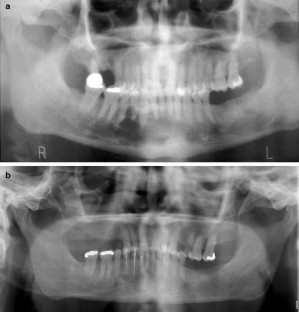

Fig. 2